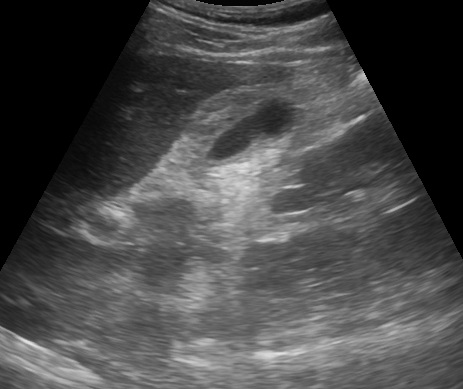

40´ë ¿©ÀÚÀÔ´Ï´Ù. ¿ÀÇÑ, ±ÙÀ°Åë, µÎÅë, ±¸¿ª°¨ »óº¹ºÎ ÅëÁõÀ¸·Î ³»¿øÇÏ¿´½À´Ï´Ù. óÀ½¿¡ AGE·Î Áø´ÜÇÏ°í ´ëÁõÄ¡·áÇϸ鼭 °æ°ú °üÂû Çϱâ·Î ÇÏ¿´°í ´ÙÀ½³¯ °í¿­ÀÌ Áö¼ÓµÇ¾î ´Ù½Ã ³»¿øÇÏ¿´°í ¼ö¾×Ä¡·á¸¸ ÇÏ°í °æ°ú °üÂûÇÏ¿´½À´Ï´Ù. 2ÀÏÈÄ ´Ù½Ã ¿Ô´Âµ¥ °í¿­ÀÌ Áö¼ÓµÇ°í ÀüüÀûÀÎ º¹Åë ¹× ±¸¿ª°¨À» È£¼ÒÇÏ¿´½À´Ï´Ù. À§³»½Ã°æ °Ë»ç¸¦ ÇÏ¿´°í À§±Ë¾çÀÌ °üÂûµÇ¾úÀ¸³ª ¹ß¿­ µîÀÇ Áõ»óÀÌ À§±Ë¾çÀ¸·Î ¼³¸íµÇÁö ¾Ê¾Æ º¹ºÎ ÃÊÀ½ÆÄ °Ë»ç¸¦ ÇÏ¿´°í Liver S8¿¡ 3.5*4cm Å©±âÀÇ liver abscess°¡ °üÂûµÇ¾î »ó±ÞÀÇ·á±â°üÀ¸·Î ÀÇ·ÚÇÏ¿´½À´Ï´Ù. Áø´ÜÀÌ Áö¿¬µÇ¾î ȯÀÚ¿¡°Ô ¿ø¸ÁÀ» µé¾ú´ø ÄÉÀ̽º Áß ÇϳªÀÔ´Ï´Ù.